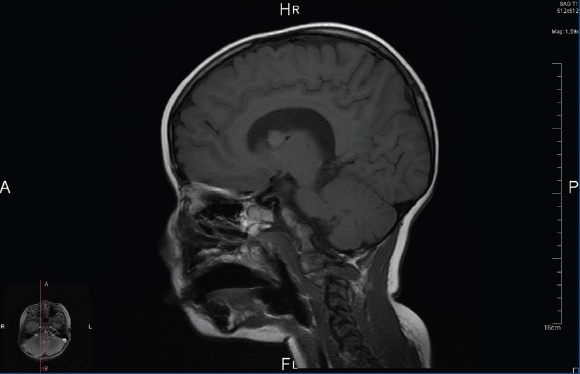

La resonancia magnética (RM) craneal (Fig. 2)muestra una imagen nodular de 11 mm cercana al agujero de Monro derecho, correspondiente a un astrocitoma subependimario de células gigantes (SEGA).

Figura 2. RM craneal: imagen nodular de 11 mm de diámetro cercana al agujero de Monro